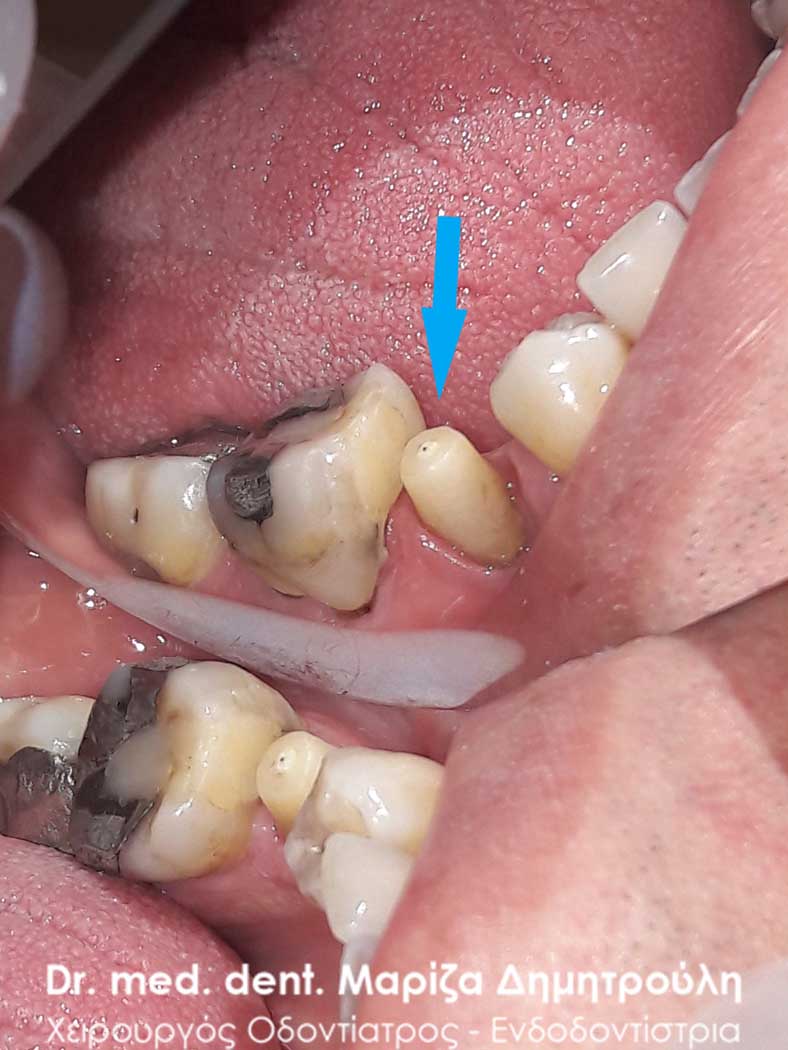

Περιστατικό – Ολοκεραμική θήκη ζιρκονίου στον αριστερο γομφίο της κάτω γνάθου

Ο πρώτος γόμφιος στην αριστερή πλευρά της κάτω γνάθου είχε απονευρωθεί στο παρελθόν. Ο ασθενής δεν θέλησε να καλύψει το δόντι με θήκη, ώστε να είναι πλήρως προστατευμένο με αποτέλεσμα το δόντι να σπάσει (όπως φαίνεται στην αρχική εικόνα). Η λύση θεραπείας ήταν η κατασκευή στεφάνης δοντιού, αφού προηγουμένως το δόντι τροχίστηκε καταλλήλως και ο οδοντοτεχνίτης κατασκεύασε την ολοκεραμική θήκη ζιρκονίου.

Το δόντι είναι πλέον πλήρως προστατευμένο και μπορεί να αντέξει στο πέρασμα των χρόνων.

ΠΡΙΝ